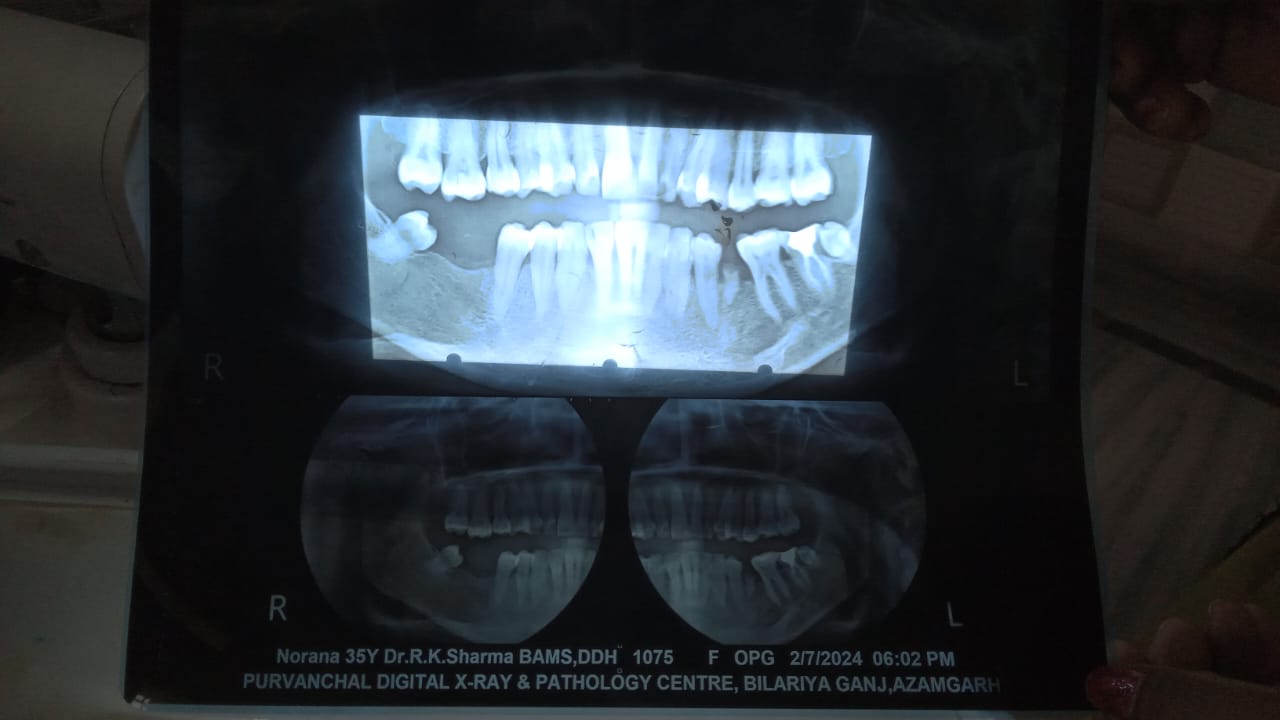

We recommend a routine dental check-up every 6 months to maintain optimal oral health and catch potential issues early before they become serious.